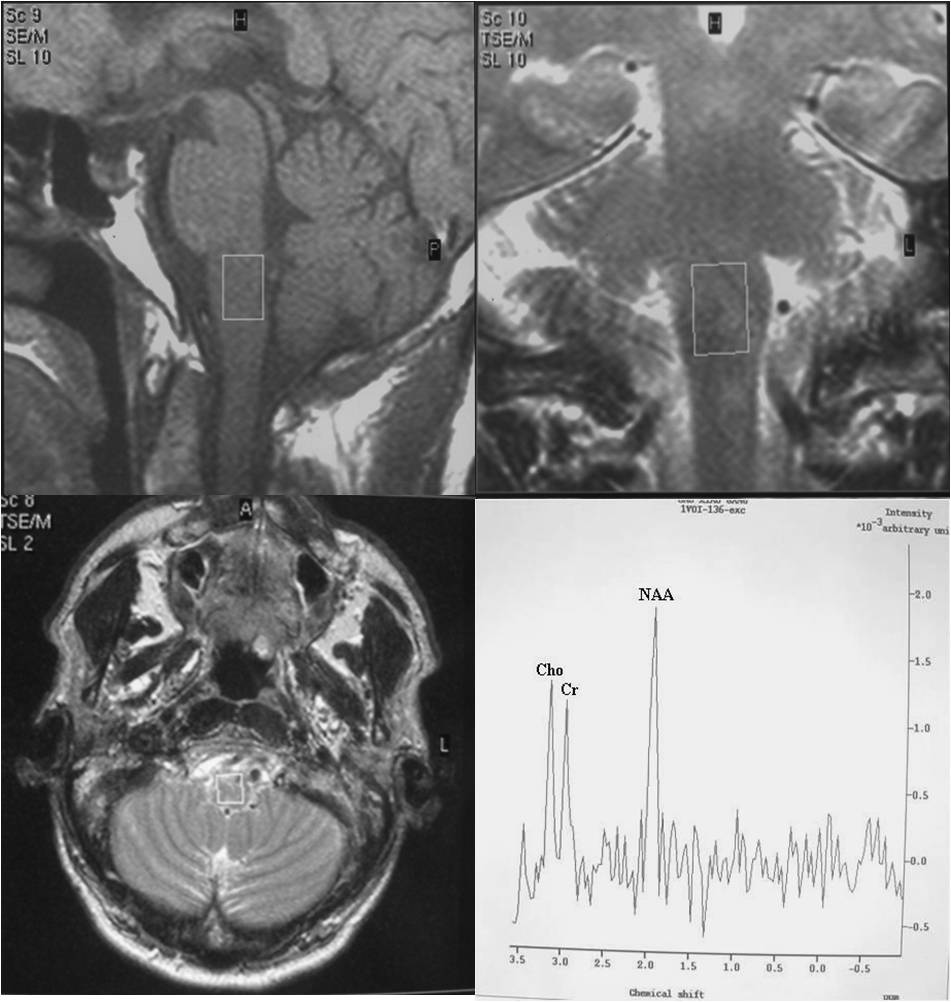

Objective: To use 1.5T 1H-MRS as a research tool in vivo and demonstrate the feasibility of obtaining long-echo 1H MR spectra in small volumes like substantia nigra (SN) and medulla oblongata (MO) in healthy volunteers and patients with Parkinson's disease (PD) and observe the clinical correlations.

Subjects and Methods: Twenty patients of the idiopathic Parkinson’s disease (IPD) were recruited from the Out Patient Department of Neurology. Additionally, 14 age-matched healthy subjects were taken as controls group. After baseline evaluation, the patients satisfying inclusion and exclusion criteria underwent 1H-MRS study. All MR examinations were performed on a 1.5 T system (Philips Gyroscan Intera, Netherlands) using a standard quadrature head coil.

Results: We succeeded to achieve 74.19% and 77.42% of spectra from MO and SN of both PD and control groups. MO showed slightly weak negative result to total UPDRS and UPDRS- II, but no significant correlation was found between metabolites and clinical indexes in MO. The result also showed no significant correlations between H&Y scale and metabolites in MO and SN of PD patients. But there was a significant correlation between H&Y, NAA/Cr and Cho/Cr in SN.

Conclusions: MRS ratios from MO and SN does not play any significant role to differentiate PD from the normal subjects, but metabolites ratios from SN of PD patient can help to understand the progression and severity of the disease. Therefore, it is not practical to employ MRS as a diagnostic tool for PD.